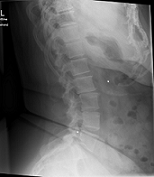

Röntgenbilder

- Dateianhänge

- TSPINE

- TSPINE vk II.png (22.24 KiB) 19770 mal betrachtet

deine Bilder lassen vermuten, dass vielleicht gar nicht die Skoliose dein Problem ist, sondern dein sagittales Profil. (Steht dein Kopf ziemlich nach vorne, wenn du dich vin der Seite betrachtest?) solltest auf jeden Fall einmal zum Spezialisten, im deine Situation kompetent abklären zu lassen. Aus NRW ist wahrscheinlich Dr. Verres in Bingen am nächsten.

mit dem sagittalen Profil meint man das Profil von der Seite gesehen. Laut deinen Aufnahmen hast du eher eine geringe Skoliose, aber einen ziemlichen Rundrücken und Hohlkreuz was auch Beschwerden machen kann und das die Ärzte auch gerne übersehen oder nicht sehen wollen. Deshalb ist es auch wichtig, einen Spezialisten aufzusuchen, der dies auch mit behandeln kann. Leider ist dies keine Ganzaufnahme, dann würde man das eher sehen. Es gibt hier schon genug Berichte, die das mit Hyperkyphose und -lordose gut beschreiben. Also lesen bildet...

Dem kann ich mich nur anschliessen, es sieht sehr nach Rundrücken (Bild 2-Hyperkyphose) und Hohlkreuz (Bild 1-Hyperlordose) aus.sloopy hat geschrieben:deine Bilder lassen vermuten, dass vielleicht gar nicht die Skoliose dein Problem ist, sondern dein sagittales Profil.